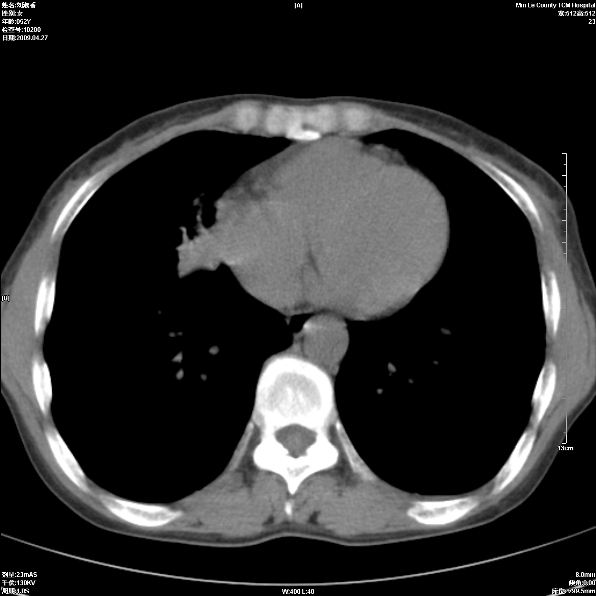

标题: CT19625:女52间断性喀血 [打印本页]

标题: CT19625:女52间断性喀血

考虑右肺中叶感染性病变并右肺中、下叶肺泡积血;建议抗炎、止血治疗后复查。

右肺中叶炎症;右肺中、下叶肺泡积血

右肺中叶支气管扩张并感染或咳血沉积,块右肺中下叶肺泡积血。

右肺中叶慢性炎症伴局部支扩并中下叶肺泡积血。

考虑右肺中叶感染性病变并右肺中、下叶肺泡积血。建议治疗后复查。